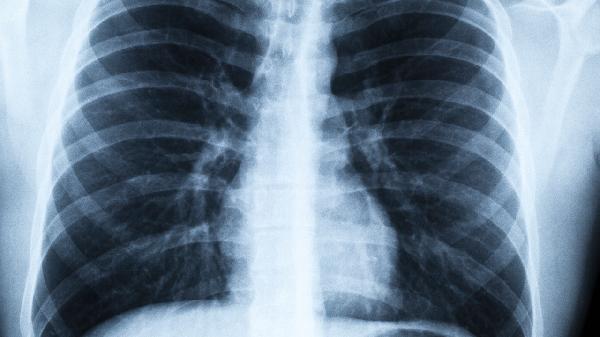

肺结节这个词近年来频繁出现在体检报告中,让不少人提心吊胆。其实肺结节就像皮肤上的痣一样常见,但确实需要科学对待。今天我们就来聊聊这个藏在肺部的小“阴影”,到底该如何正确应对。

体检发现的肺结节90%以上都是良性的,可能是肺部炎症、结核等留下的疤痕,或者是血管的影像重叠。只有不到5%的肺结节最终会确诊为恶性。

小于5毫米的微小结节恶性概率极低,5-10毫米的结节需要定期随访,大于10毫米的结节才需要特别关注。

边缘光滑的结节多为良性,而边缘毛糙、有分叶、毛刺等特征的结节需要警惕。